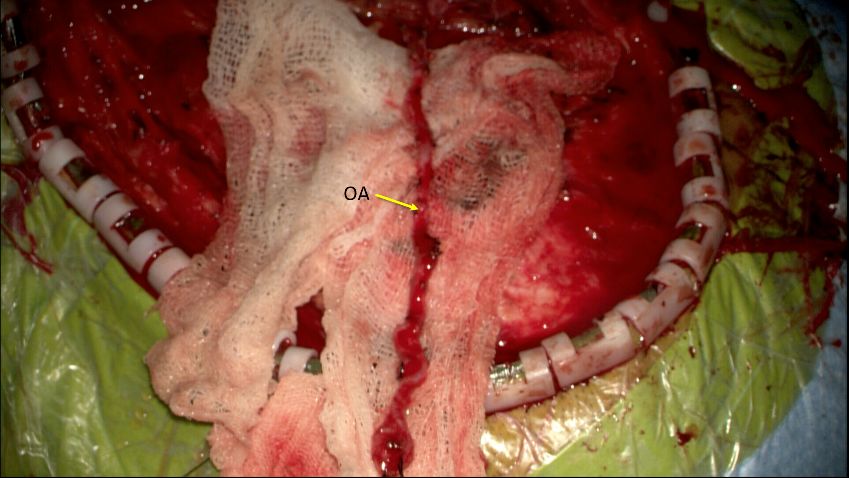

2. 翻开皮瓣,显微镜下游离枕动脉备用。

3. 行左侧枕下骨窗成型,咬开C1后弓侧方。剪开硬膜,翻向颅底,向上牵开小脑扁桃体,即可暴露VA起始部及PICA血管袢。继续向上方游离,于后组颅神经深面即可见动脉瘤。动脉瘤位于VA-PICA起始部,PICA起源于瘤体。

4. 临时动脉夹夹闭枕动脉近端,及PICA血管袢近端及远端。枕动脉45度剪开,修剪血管后行枕动脉-PICA端侧吻合。取除临时动脉瘤夹,多普勒超声明确桥血管通畅。